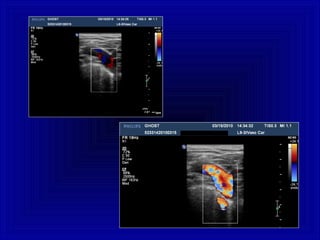

Arterie , piccoli vasi , profondi ,Arterie , piccoli vasi , profondi ,

bassa velocità , bassa resistenzabassa velocità , bassa resistenza

DISTRETTODISTRETTO

RENALERENALE

REGOLAZIONEREGOLAZIONE Bassa Frequenza ,bassa PRF, WF bassi

Arterie, grossi vasi, superficiali , altaArterie, grossi vasi, superficiali , alta

velocità, alta resistenzavelocità, alta resistenza

Vene, grossi vasi , superficiali , bassaVene, grossi vasi , superficiali , bassa

velocità, flusso continuovelocità, flusso continuo

ARTIARTI

INFERIORIINFERIORI

REGOLAZIONEREGOLAZIONE Alta Frequenza,Alta Frequenza,

Alta PRF,Alta PRF,

Bassa PRF,Bassa PRF,

WF medio-altiWF medio-alti

WF medio-bassiWF medio-bassi